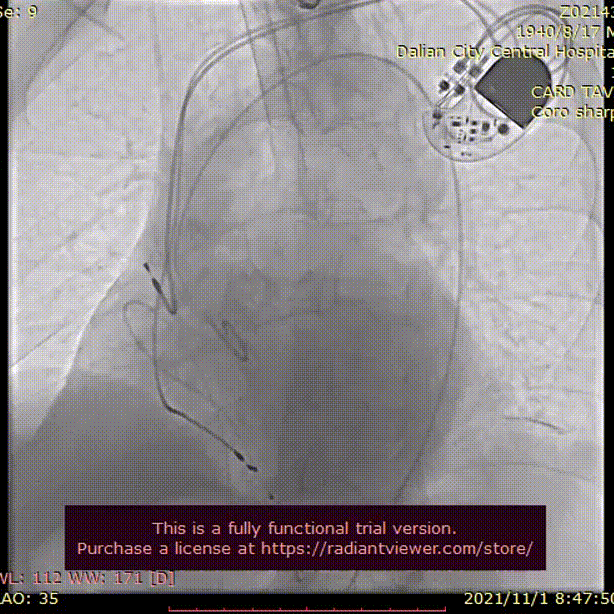

术中影像

22mm球囊充分扩张

瓣膜初始定位, 选择0位释放

TaurusElite AV26mm瓣膜,瓣上2mm 工作位造影

瓣膜形态良好 位置理想